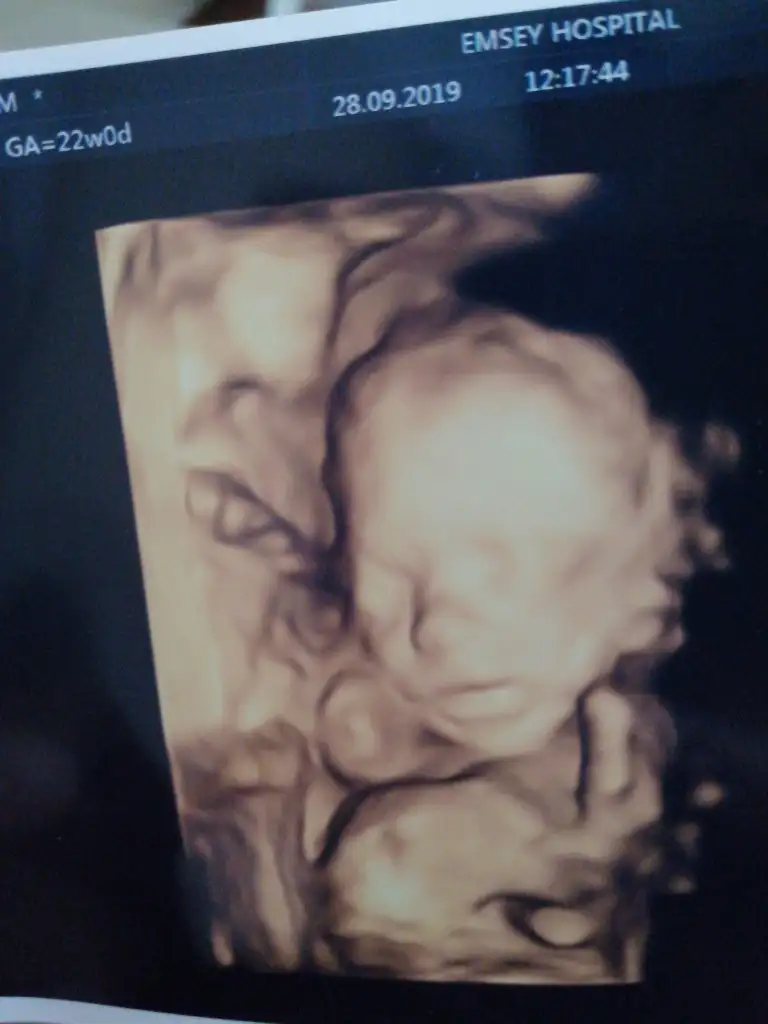

Bu da bizim uyuyan güzelimiz

Eki Görüntüle 2540352